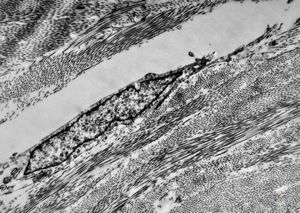

F,41y. | synovial metaplasia - capsule of implantate